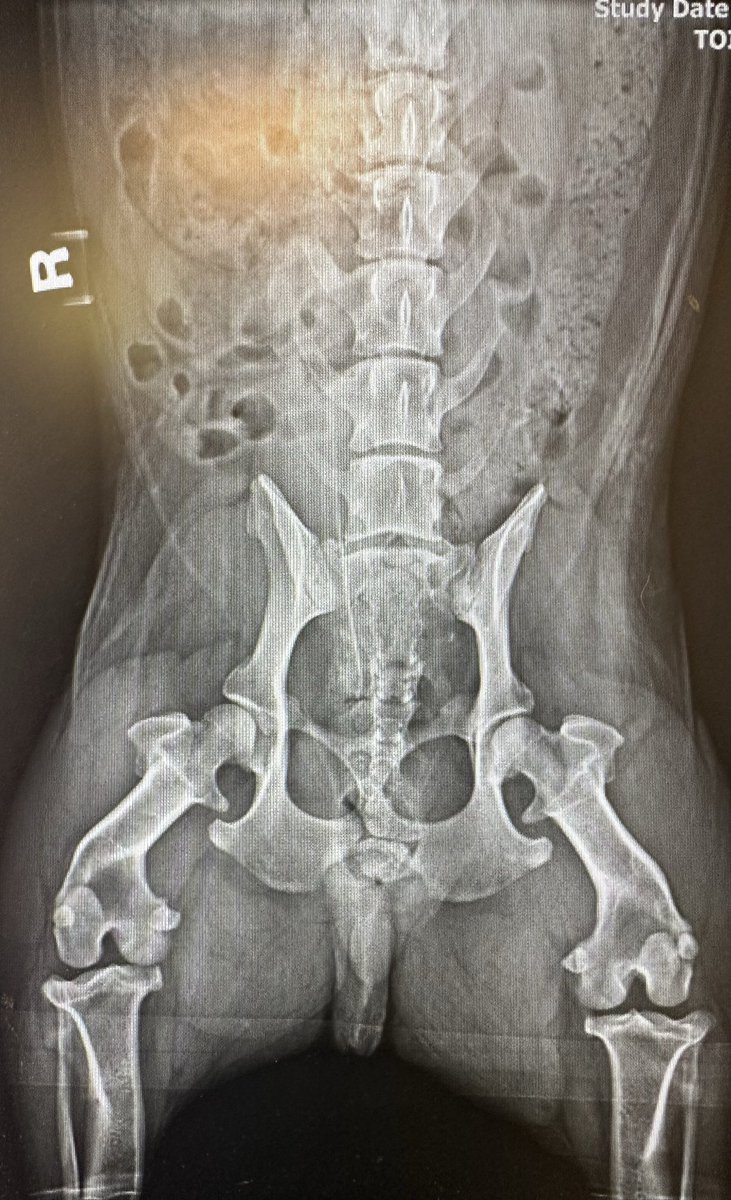

In case anybody was curious what a Corgi's L-spine and hips look like under x-ray. I was. #CorgiRad

Jacob Fleming, MD tweet mediaJacob Fleming, MD tweet media